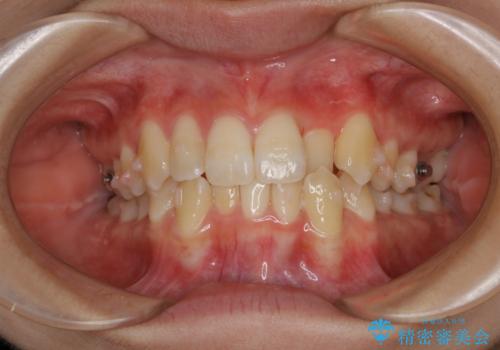

- 上の前歯が1本後ろに入ってしまっていることが気になるとご相談にいらした方です。

元々下の前歯が1本欠損しており、上下の噛み合わせや、歯のサイズバランスを考慮しながら治療を行いました。

クロスバイトしている歯が深く噛み込んでおり、この歯を外に出してくる際に強い咬合力が加わると歯が失活する恐れがあることを説明し、合わせて咬筋へのボトックス注入を行いました。

下顎切歯が1本欠損しているため、上顎前歯部を少しずつストリッピングして、上下の噛み合わせ、バランスの向上を図りました。